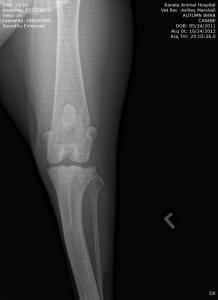

UPDATE: I know I have much to update in BHRR's Autumn's blog and before I go to bed in the wee hours; I shall update her blog plus add photos from her x-rays – taken of both legs, chest, back, legs, heart etc. on October 24th, 2012 and you can find them below! 🙂

From there, we are putting our creative hats on as she will need two cruciate surgeries – $6,000-$7,000+ – and the specialist is still looking at those eyes and what is going to be best….

She has three surgeries ahead of her – a spay and two separate cruciate surgeries and this is in addition to her almost $3,000 bills to date that have been racked up.